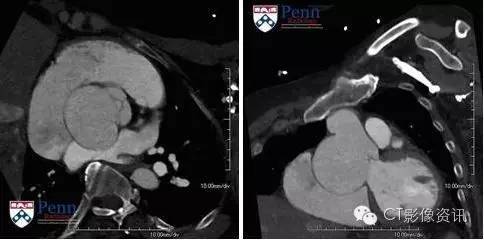

表现 回顾性心电门控冠脉CTA,可从79%期相的舒张末期图像中显示出主动脉根部扩大继发于非冠状窦瘤。扩大的窦口长径约6.4cm、横径约4.1cm。整个主动脉根部大小约6.9×7.3cm。

最终诊断:主动脉窦瘤--非冠状动脉窦

主动脉窦瘤诊断要点 主动脉窦位于主动脉环和窦管交界之间。 它与右冠状动脉窦,左冠状动脉窦和无冠状动脉窦都有相关联。 主动脉窦瘤相对较罕见,患病率仅有1%。 它可能是先天性(Marfan、Ehlers-Danlos等)或是获得性(感染、动脉粥样硬化、创伤等)。 先天性动脉瘤可能与其他心脏异常有关,如室间隔缺损(VSD),二叶主动脉瓣(Cogenital Bjcuspid Aortic Valve, CBAV)及冠状动脉异常。 这个疾病多见于亚洲男性。 动脉瘤可以通过超声心动图,CT血管造影,磁共振血管造影或常规血管造影进行评估。 如进行冠脉CTA首选使用心电门控以减少在主动脉根部的运动伪影,并观察是否有出现其他并发症。 它通常会表现为窦囊外翻,升主动脉和邻近主动脉根部的内径正常。 一般可无临床症状,或表现为动脉瘤破裂的症状。 对未破裂的动脉瘤的并发症包括主动脉瓣关闭不全,三尖瓣、二尖瓣关闭不全,心律失常,心室流出道阻塞,大动脉原性脑梗塞,继发于冠状动脉压迫的心肌缺血/梗塞等。 动脉瘤破裂后进入右心室比右心房多,从而导致心脏左到右分流和心脏衰竭。 动脉瘤破裂后一般需要手术治疗,通常多采用补丁修复。 对于未破裂的动脉瘤修复手术的适应症包括较复杂的并发症状,如流出道梗阻、缺血和心律失常。 目前,对未破裂的动脉瘤修复手术还没有一定的手术标准,但在修复未出现并发症的大动脉瘤时仍旧要谨慎。